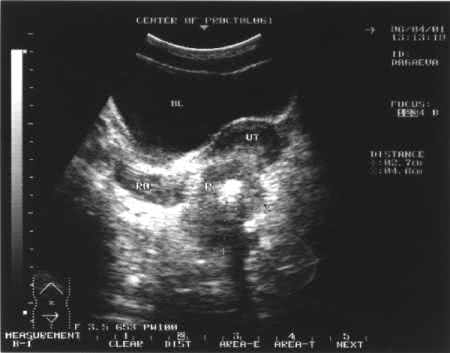

- УЗИ органов малого таза. Исследование позволяет обнаружить поражение соседних органов и лимфоузлов.